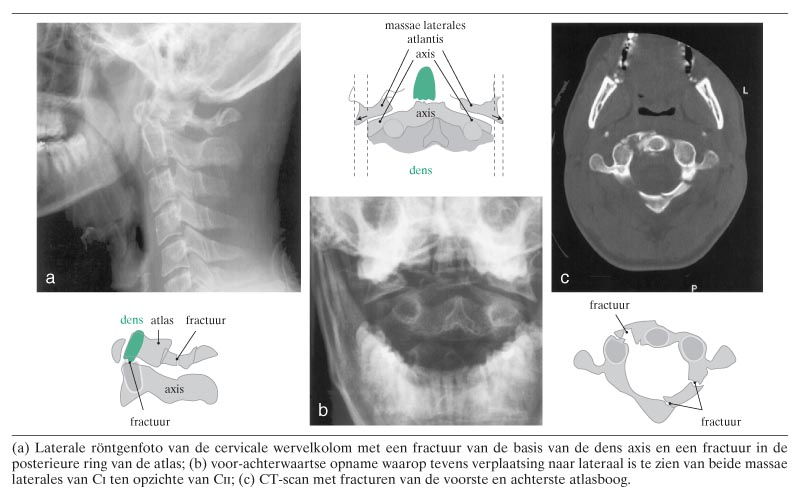

Een 24-jarige man kwam tijdens het mountainbiken ten val en belandde op zijn hoofd in een ondiepe sloot. Hij had pijn in de nek, zonder motorische of sensibele uitval. De laterale röntgenfoto van de cervicale wervelkolom toonde een fractuur van de basis van de dens axis met een matige knikstand naar dorsaal (figuur a). De voor-achterwaartse foto liet tevens verschuiving naar lateraal zien van de beide massae laterales van CI ten opzichte van de overeenkomstige delen van CII (zie figuur b). Dit beeld wees op een verbrijzelingsfractuur (‘burst’-fractuur) van CI, ook wel…